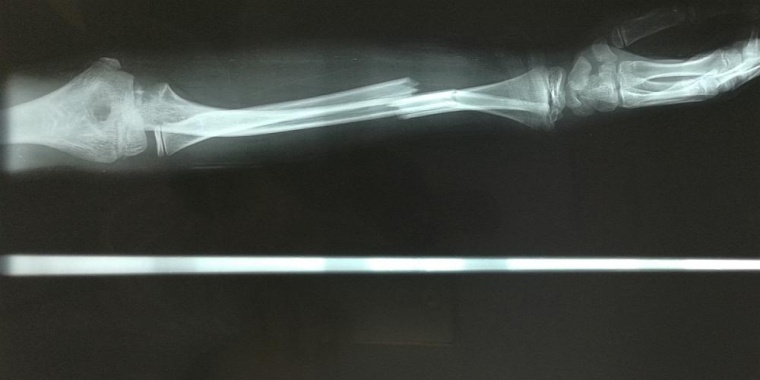

Die meisten Knochenbrüche heilen vollständig und ohne Narbenbildung aus. Besonders große Knochendefekte, die durch schwere Verletzungen, eine Infektion oder eine Tumoroperation entstanden sind, heilen jedoch oft nicht auf natürliche Weise und machen eine Knochentransplantation erforderlich. Mit weltweit etwa zwei Millionen Transplantationen pro Jahr sind Knochen nach Blut das am zweithäufigsten transplantierte Gewebe. Die Verfügbarkeit von Transplantaten ist jedoch begrenzt und ihre Regenerationsfähigkeit häufig gering. Eine vielversprechende Alternative sind zellbasierte Therapien. Im Labor hergestelltes Gewebe aus Vorläuferzellen wie den sogenannten multipotenten Stromazellen (MSC) könnte die üblichen Knochentransplantate ersetzen. Dass das funktioniert, konnten jetzt Forscher*innen des Berlin Institute of Health in der Charité (BIH) gemeinsam mit Kolleg*innen von der Paracelsus Medizinischen Privatuniversität (PMU) Salzburg zeigen. Entscheidend dabei: Es ist nicht egal, aus welchem Gewebe – Fett, Haut oder Knochen – diese Stromazellen entnommen werden.

„Der Knorpel, den wir in der Kulturschale herstellen können, entspricht einem wichtigen Zwischenprodukt für die Bildung von mineralisiertem Knochengewebe. Wir konnten bei Mäusen zeigen, dass die Transplantation der vitalen menschlichen Knorpelscheiben zu einer vollständigen Heilung von großen Knochendefekten führt“, sagt Dr. Sven Geissler vom BIH Center für Regenerative Therapien und einer der Senior-Autoren der Studie. „Im Tier bilden die transplantierten menschlichen Zellen in den Knorpelscheiben auch das initiale Knochengewebe, das am Ende der vollständigen Heilung durch körpereigene Zellen der Maus ersetzt wird.“